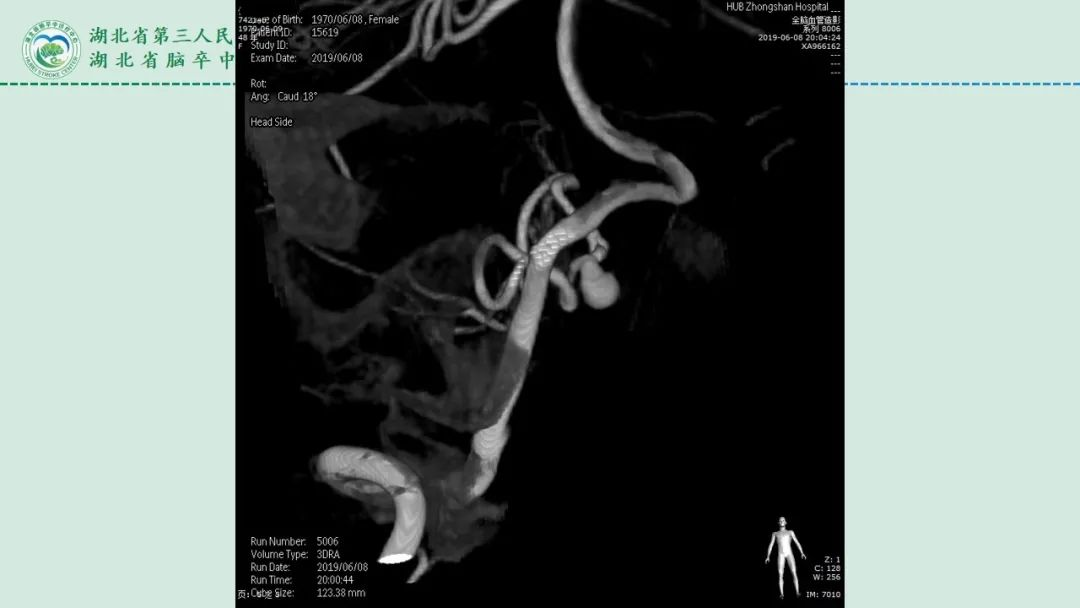

李俊教授团队:右侧PICA延髓扁桃体段多发动脉瘤

今日与大家分享的是《正海-妙术视界》第二百三十二期,由湖北省第三人民医院李俊教授团队带来的右侧PICA延髓扁桃体段多发动脉瘤,欢迎观看、分享。